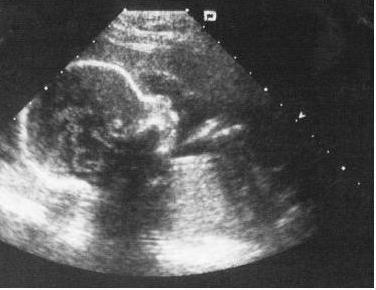

Кожна вагітна жінка схильна до ризику передчасних пологів, але більшість думають, що це ніколи не трапиться з ними. Коли вони стикаються з цим, то згадують про профілактику і додаткових дослідженнях. Самим доступним і нешкідливим дослідженням є УЗД, при якому лікар може поставити діагноз загрозливих передчасних пологів.

Численні дослідження показали, що УЗД-показник шийки матки приблизно з 20 до 24 тижнів вагітності – це сильний індикатор передчасних пологів. Довжину шийки матки найбільш точно можна виміряти з допомогою трансвагінального УЗД. Якщо жінка не вагітна, то розміри шийки матки по УЗД (норма) становлять близько 4 див.

Більшість лікарів призначить жінці трансабдомінальне УЗД на терміні близько 20 тижнів. Якщо довжина становить менше 4 см, роблять трансвагінальне УЗД, щоб отримати більш точне вимірювання.

Коротка шийка матки між 20 і 24 тижнями – небезпечний симптом.

За допомогою трансвагінального УЗД можна побачити як зверху, так і знизу шийку матки. У цьому випадку вона виглядає як воронка. Широка частина воронки знаходиться найближче до тіла матки, а найвужча частина розташована в напрямку до піхви. Коли шийка матки скорочується ще більше, це буде виглядати як “V” на УЗД.

У нормі шийка матки має форму трубки. Більше ніж у 50 відсотків вагітних при патології цього органу виникають передчасні пологи.